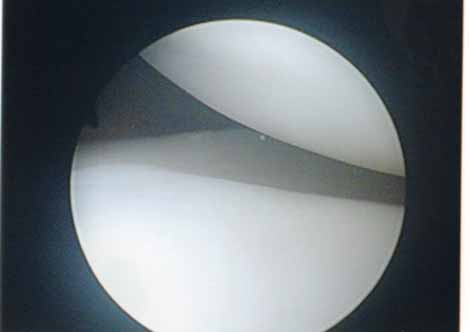

外側円板状半月損傷

外側円板状半月損傷は水平断裂で始まり、強い症状に発展したときは複合断裂になっていることが多くなります。長期経過例では変形性変化を合併することが多くなります(Okazaki 2006)。このタイプの半月板は切れ始めたら正常にできるだけ近い半月板に形成します。手術は関節鏡手術で手術翌日に松葉杖なしで退院出来ます。

完全型円板状半月遊離縁

右:円板状半月